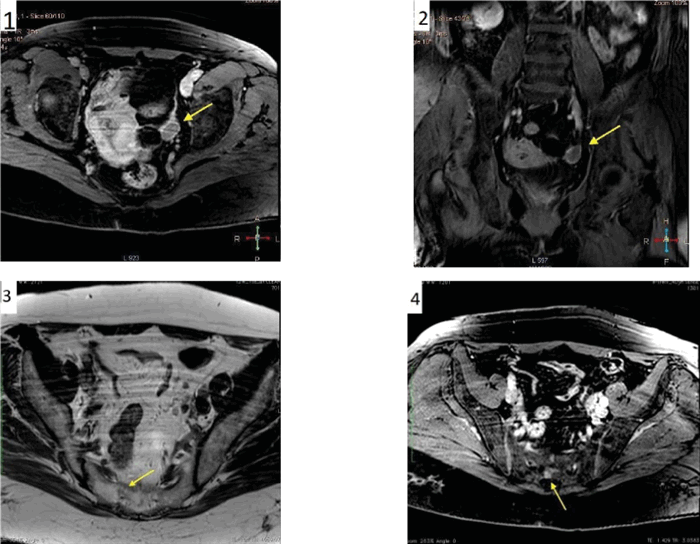

Проведен онкопоиск. При ультразвуковом исследовании обнаружен объемный процесс в полости малого таза слева. По данным магнитно-резонансной томографии выявлены гиперпластические изменения в эндометрии, объемное образование левой тубовариальной области, патологические изменения в костях таза (вероятно, метастатического генеза) (рис. 1).

Рисунок 1. МРТ органов малого таза: Т1 с контрастным усилением в аксиальной (1) и коронарной (2) проекциях — стрелками обозначена опухоль левого яичника; на Т2 в аксиальной проекции (3) стрелкой обозначена зона патологических изменений в правых отделах крестца; в режиме Т1 с контрастным усилением (4) в аксиальной проекции стрелкой обозначена зона накопления контраста в правых отделах крестца (предположительно — метастаз).